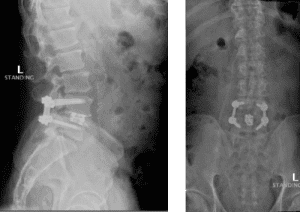

His MRI lumbar spine showed a herniated disc at L2/L3 and a grade 1 spondylolisthesis at L4/L5. Both of these findings were contributing to the patients back and leg pain.

Image 1A shows central stenosis at L4/L5 level associated with grade 1 spondylolisthesis.

Image 1B shows disc herniation at L2/L3.

Image 3. Post-op x-rays that show L4/L5 transforaminal lumbar interbody fusion (TLIF). There was also removal the L2/L3 disc herniation but no need for instrumentation.

Dr. Imani was able to decompress both the L2/L3 level (with disc herniation removal) and the L4/L5 level. Additionally, L4/L5 level was fused using titanium screw and an expandable interbody cage. This was performed with a very small incision. The patient has no more leg pain and back pain, and is doing very well!